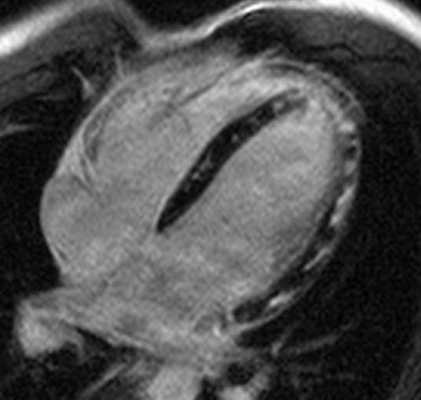

Рисунок 3. МРТ. Четырехкамерное сечение сердца. Апикальная гипертрофия миокарда левого желудочка.